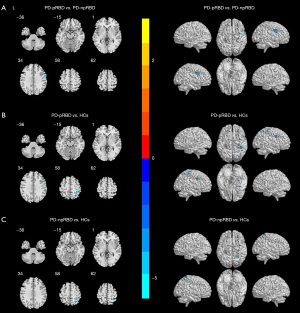

DC evaluations showed that the z-DC values of the right precentral gyrus decreased in PD-pRBD patients weighed against those in PD-npRBD group (Figure 1, Table 2). Along with the right precentral gyrus, PD-pRBD also exhibited lower z-DC values in the right postcentral gyrus and the superior parietal lobule than the HCs. Additionally, z-DC in the right superior parietal lobule was significantly reduced in the PD-npRBD group in comparison to the HCs group. Notably, the z-DC values of the right precentral gyrus in PD-pRBD patients were negatively correlated to the RBDSQ scores (Figure 2A), whereas there was no correlation with UPDRS-III scores (Figure 2B). Moreover, we did not discover a correlation between RBDSQ scores and MMSE (Figure 2C) or HAMD-24 scores (Figure 2D).

Figure 1 Significant differences of DC result maps among three groups: PD-pRBD, PD-npRBD, and HCs. Statistical threshold was displayed at voxel-level P value <0.001, Gaussian random field corrected, cluster-level P value <0.05. Cool colors represent significantly decreased DC. (A) Differences between PD-pRBD and PD-npRBD; (B) differences between PD-pRBD and HCs; (C) differences between PD-npRBD and HCs. L, left; PD, Parkinson’s disease; PD-pRBD, Parkinson’s disease with probable rapid eye movement sleep behavior disorders; PD-npRBD, Parkinson’s disease without probable rapid eye movement sleep behavior disorders; HCs, healthy controls; DC, degree centrality.

There was a reduction in EC from the right precentral gyrus to the right caudate nucleus in PD-pRBD patients contrasted with PD-npRBD patients (Figures 3,4, Table 3). Further, correlation analysis demonstrated that EC values from the right precentral gyrus to the ipsilateral caudate nucleus were negatively related to the RBDSQ scores (Figure 5A), whereas there was no correlation with UPDRS-III scores (Figure 5B). In contrast, no statistically significant disparity in EC was noticed between the PD groups from the whole brain to the right precentral gyrus.

Figure 3 Significant differences of EC result maps among three groups: PD-pRBD, PD-npRBD, and HCs. Statistical threshold was displayed at voxel-level P value <0.01, Gaussian random field corrected, cluster-level P value <0.05. Cool colors represent significantly decreased EC, whereas warm colors represent the opposite. (A) differences between PD-pRBD and PD-npRBD; (B) differences between PD-pRBD and HCs; (C) differences between PD-npRBD and HCs. L, left; PD, Parkinson’s disease; PD-pRBD, Parkinson’s disease with probable rapid eye movement sleep behavior disorders; PD-npRBD, Parkinson’s disease without probable rapid eye movement sleep behavior disorders; HCs, healthy controls; EC, effective connectivity.